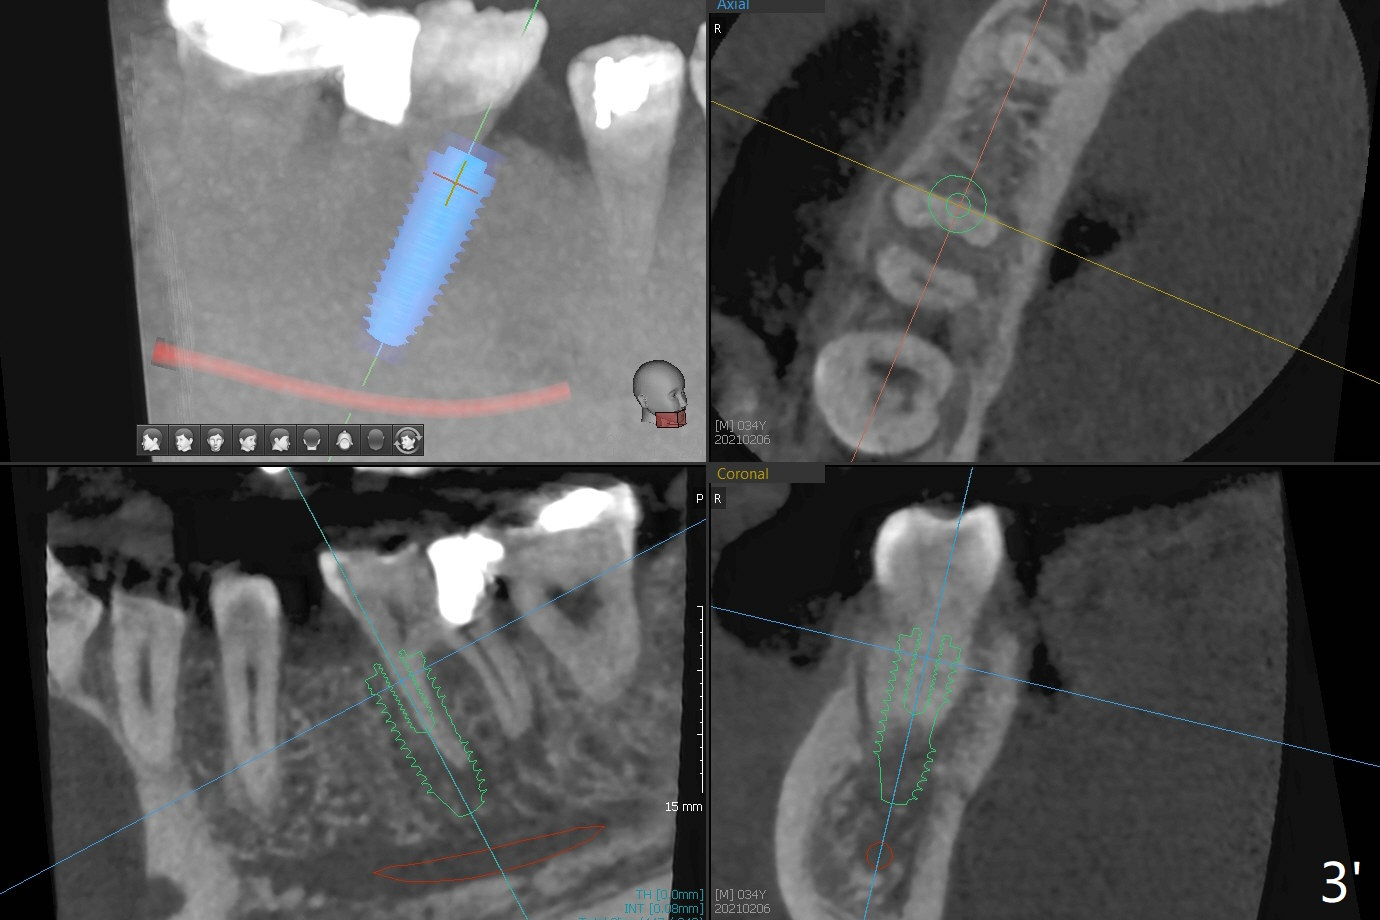

35岁男牙齿矫正后2年5个月右下6远中深龋,拔除后,近中根尖肉芽组织(图零(术前CT冠状切面):*)刮除疼痛,必须阻滞麻醉才能控制疼痛,可能与下牙槽神经分支(图零:红箭头)有关。原先准备在近中牙槽窝近中种植(5x11.5mm),术中发现近中牙槽窝种植好像方便,位置不错,不由自主在那里开始钻洞,由于牙槽窝深,钻洞必须13毫米(图一(接近神经:红虚线)),之后发现钻洞(图二(术前CT3D长轴切面(黑色:近中,远中牙槽窝)):红圆圈)不够理想,使用Lindamann Bur将钻洞往颊侧近中移动(图二:箭头),最终在这方面结果可以(图三,三’,四),虽然接近神经,术后没有神经麻痹。放置粘性骨粉(图四:*),PRF膜,4-0 PGA缝线(图五),最后使用树脂敷料(图六:A)。后牙垂直空间少,术后一周需要降低树脂敷料高度(图七)。术后一个月取出敷料,牙槽窝愈合,植体平台远中稍微暴露(图八),准备一个月后制作临时牙冠。术后两个月植体远中没有暴露,但是基台远中边缘太高了(图九:>),换成6x4毫米愈合基台。下个月换成袖短的修复性基台,安置临时牙冠,牵拉7。舌侧cleats之间放置power chains,颊侧power hooks。其实术后4个月安置临时牙冠和band(图十),牙冠牙合面加高,这样7可以无阻挡移动(图十一:*;16x22 arch wire)。7远中放置power hook行不通,因为末端碰到颊侧前庭牙龈,造成创伤。只好用7颊侧原有牵引勾,在6近中安置一个短的power post (? 图十:箭头),按常规post往下,之间放置12毫米closed spring。如果post往上安置,7牙根牵引可能更有效?近中牵引一个月,第二磨牙前移大约2毫米(图十二:^),稍微近中倾斜,closed spring从12毫米更换到9毫米,舌侧换新的power chains x 4。下一个预约,用sensor 1拍摄根尖片证实第二磨牙近中倾斜,然后在它远中16x22钢丝安放power hook,下缘向颊侧弯曲,避免接触接触粘膜。